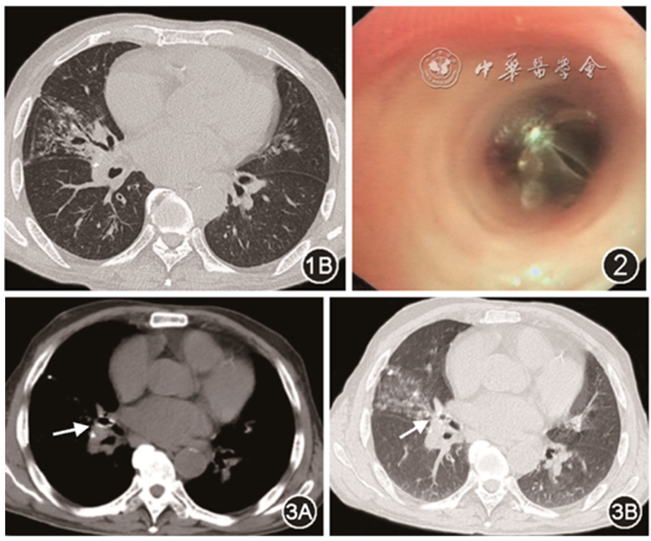

这是我们收治的一例57岁男性患者,右肺低分化腺癌,经过手术、放疗、化疗后,规律化疗住院间突发大咯血,在心肺复苏、气管插管后,在气管隆突上可见骑跨的血凝块,右侧气道被血凝块完全堵塞,结合患者肺癌病变部位,考虑右侧出血。给予球囊封堵,隔离出血源,再使用冷冻取出对侧支气管内凝血块(图8)

图片

图8  隔离健侧气道,取出血凝块

这是一例84岁支气管扩张症患者,反复发作咯血,药物/支气管动脉栓塞效果差。支气管活瓣(PulmonX Inc.,美国)置入术后出血停止,随访6个月无复发(图9)。既往关于使用单向支气管活瓣治疗咯血的报道较少,该方法有一定的优势,如操作更为简单,即使移位也不会堵塞气管或主支气管。对于合适的患者,值得进行尝试。

图9  封堵出血支气管